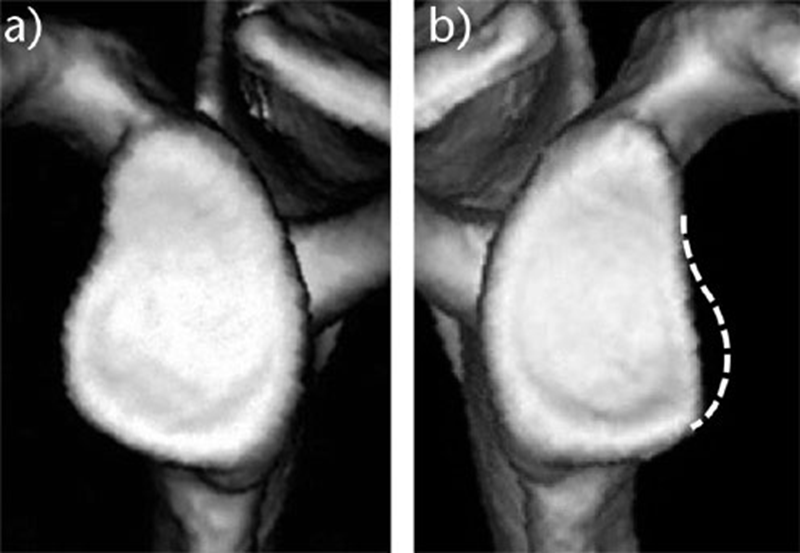

②对侧法:对侧肩(A),如果完好无损,可作为对照(虚线)(B)。

以上两种方法均可作为估算原始关节盂的形态。